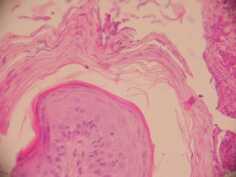

Les biopsies cutanées effectuées à l’aide d’un biopsy-punch au niveau des lésions des babines et de l’ars, (photos 5,6 et 7) montrent une dermatite superficielle périvasculaire hyperplasique avec

• hyperkératose ortho et parakératosique superficielle et infundibulaire (Photo 5)

• squamo-croûtes avec nombreuses colonies bactériennes et pustules sous-cornées

• spongiose basale diffuse d’intensité légère

• folliculite

• absence d’éléments pathogènes figurés à l’hémalun-éosine et après réaction au P.A.S.

cas-de-dermatose-amelioree-par-le-zinc-chez-une-jeune-chienne5Photo 5